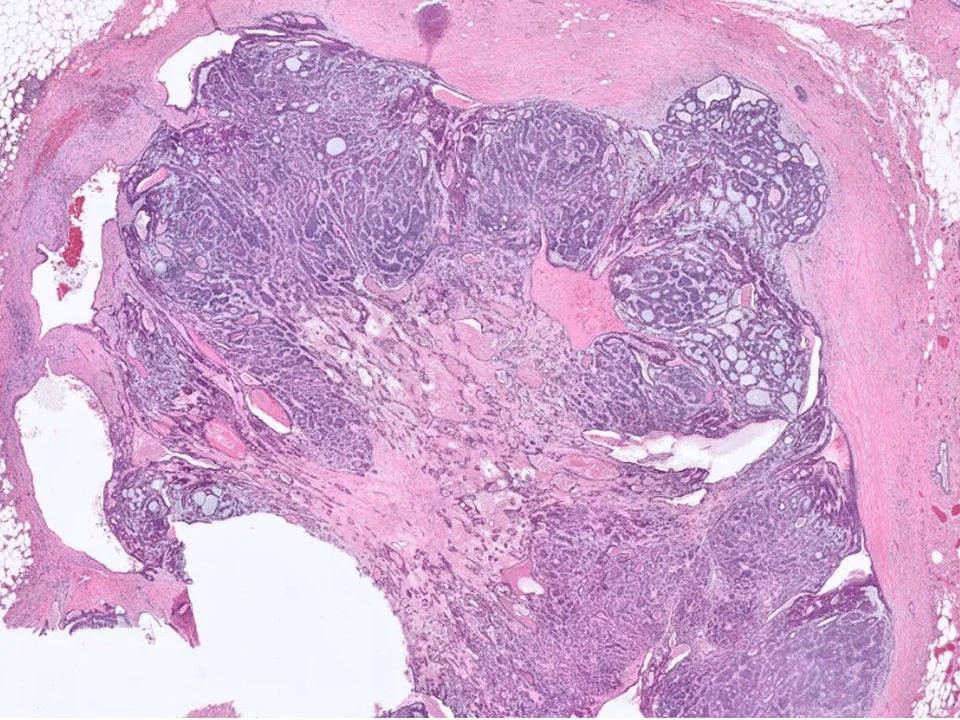

Benign Phyllodes Tumor

Phyllodes tumors are uncommon biphasic lesions that account for <1% of breast tumors. They generally occur in older women as compared to fibroadenomas, and often the patients have a history of a rapidly enlarging tumor. They tend to be larger than fibroadenomas, although this is not a hard and fast rule.

Histologically, phyllodes tumors are characterized by stromal hypercellularity and prominent intracanalicular growth pattern, sometimes with branching, cleft-like spaces.